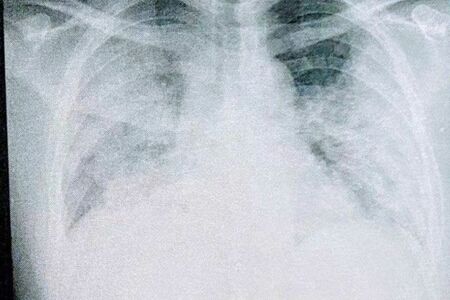

「しかしその後、自分の肺のレントゲン写真を見せられて愕然としました。全体が真っ白で、1/4しか肺が機能していなかったんです。自力では酸素をまったく取り込めていなかった事実に衝撃を受けました」

この頃、瀬川さんは自分のレントゲンを手持ちのスマホで撮影し、データを記録していた。

「実は、僕の父親は愛知で呼吸器内科の医師をしていました。東京と愛知で離れていますが、現在の自分の状況を伝えるために、まめにレントゲンの写真は送っていたんです。これは後から聞いた話なのですが、僕から届いたレントゲン写真を見て、父親は『もう助からないだろう』と覚悟を決めていたそうなんです。本当に驚きました」